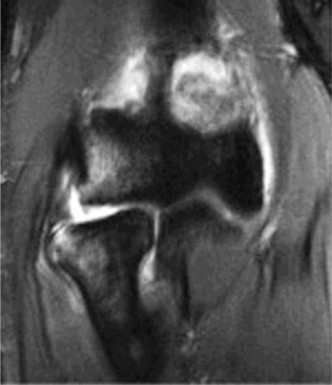

Understand common complications associated with performing surgery for scapulothoracic bursitis? CASE 33 A 42-year-old female presents to the office for follow up after sustaining a minimally displaced radial head fracture 3 months prior. She states she was initially treated in long-arm splint by the ER and did not follow up with an orthopaedic surgeon until now. Per her report, she removed the splint 4 weeks after the injury, but did not move her elbow due to pain. She now has no pain but is unable to reach that hand to her face or head. The remaining history is significant for previous ulnar nerve surgery for which she is unable to provide details. On physical examination, her upper extremity is normal except for limited flexion/extension, measured to be 80 to 50 degrees by goniometer. In addition, she has a well-healed surgical incision about the medial elbow, consistent with a previous surgery on her ulnar nerve. Her images are shown (Figs. 2–82 to 2–84).

Figure 2–82

Figure 2–83

Figure 2–84

What is the diagnosis?

- Early post-traumatic intrinsic joint contracture

- Late post-traumatic extrinsic joint contracture

- Late combined post-traumatic joint contracture

- Early combined post-traumatic joint contracture

Discussion

The correct answer is (A). Classification of post-traumatic elbow stiffness allows for better understanding of the disease and allows the clinician to treat the underlying cause of the joint contracture. Intrinsic causes include: any problem within the joint such as incongruency, loose bodies, or severe osteoarthritis. Extrinsic causes include capsular tightness, muscle contracture, heterotopic ossification, and skin contractures. Early is defined as within 6 months of the injury while late is considered to be greater than 6 months after the injury. Patients that present in the early time frame have a significantly better chance at having a good result both from nonoperative and operative treatment.